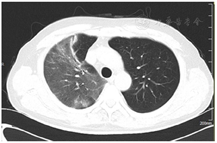

2021年7月15日复查胸部CT显示肺部感染吸收好转(图2、图3),遂停用糖皮质激素,抗生素降阶梯为头孢曲松(2 g,静脉滴注,1次/d)。BALF mNGS回报后检索惠普尔养障体感染有关文献的治疗方法亦首选头孢曲松,故继续予以头孢曲松治疗,头孢曲松治疗1周后患者病情平稳出院。院外继续长期口服甲氧苄啶磺胺甲唑(0.96 g,2次/d)治疗,停用糖皮质激素,3个月随访时患者自诉视力下降、慢性腹泻、多关节痛均得到缓解,生活质量提高。2022年3月复查胸部CT右肺上叶肺炎吸收(图4)。目前患者仍在接受口服甲氧苄啶磺胺甲唑(0.96 g,2次/d)的治疗,继续随访。